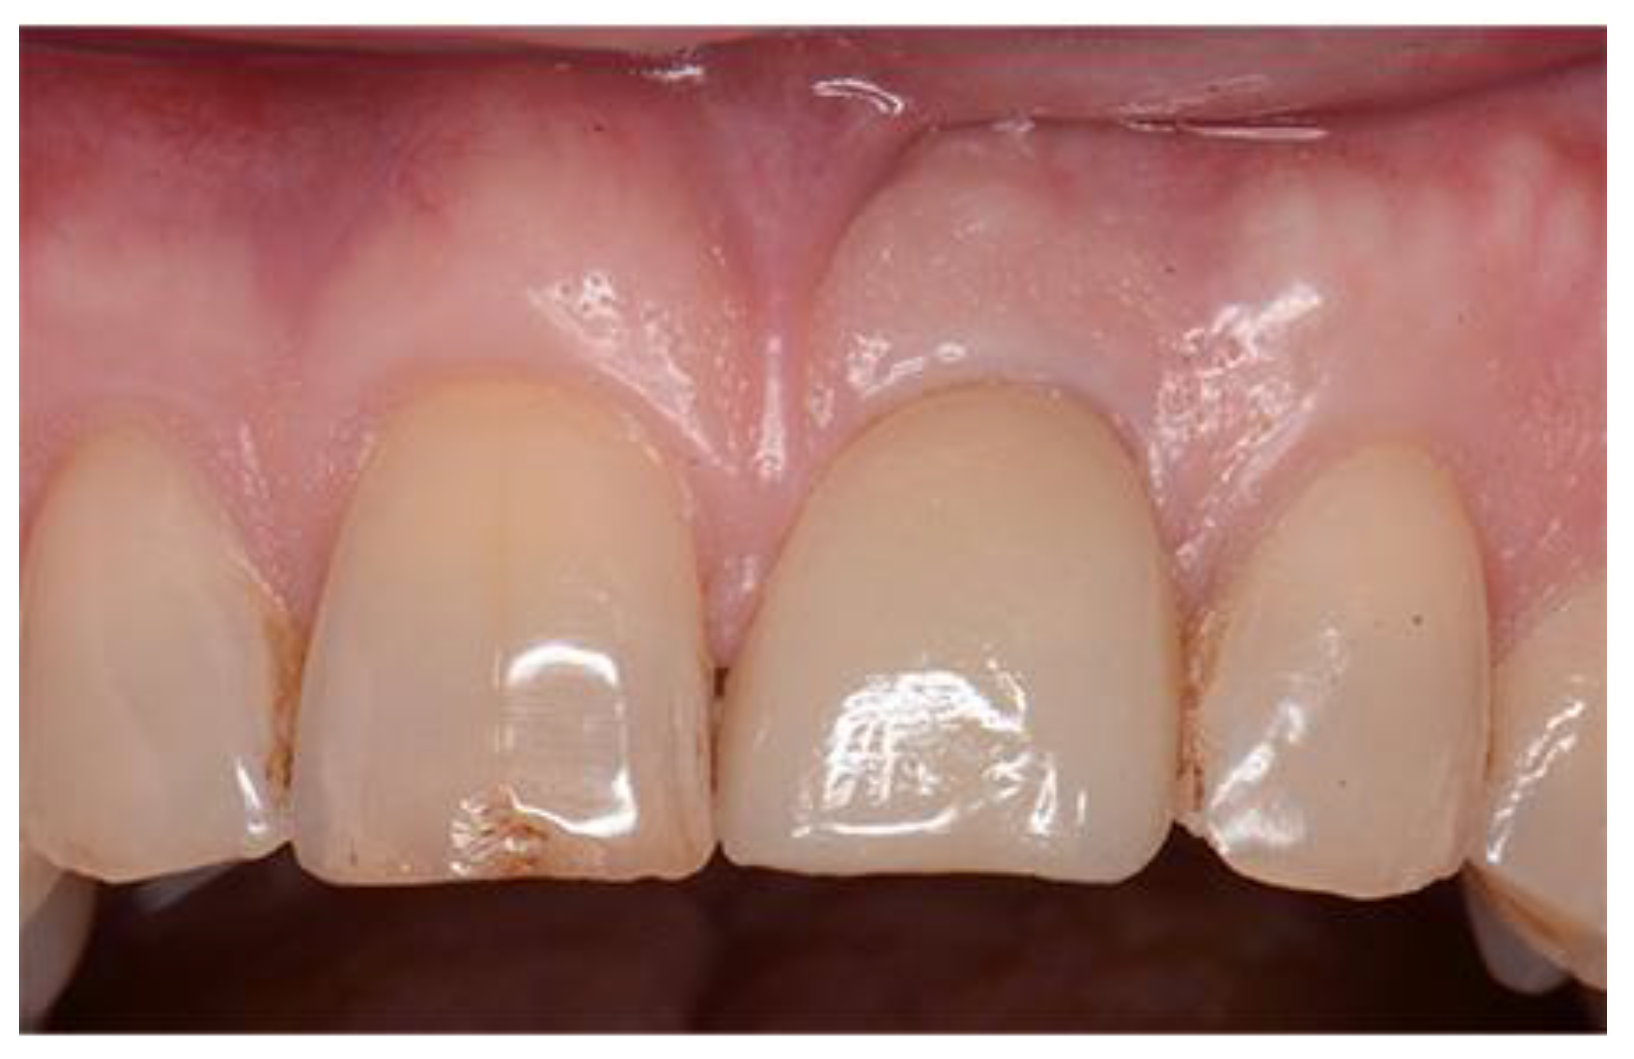

Figure 8. Preoperative image used for PES evaluation.

Preprints 86078 g007

The preoperative PES mean score was 10 with a range from 5 – 13. The postoperative PES mean at least 12 months after implant loading was 12 with a range from 10 to 14

Figure 15. Gingival architecture prior to delivery of final restoration.

Preprints 86078 g012